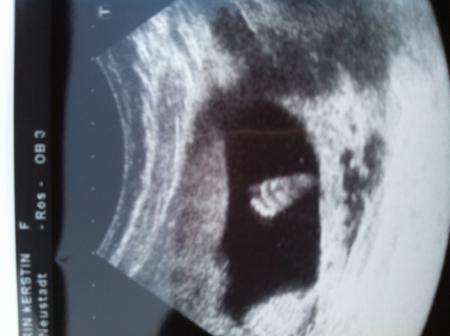

und hier noch eins vom Füßchen...

Bild zu

Oh wie süß, den erste Fußabdruck.

Der Fußabdruck ist ja echt super toll! Schön das alles Zeitgerecht ist!

Wahnsinn - das US-Bild mit den Fuß ist total Klasse! Das würde ich mir doch glatt an die Wand hängen < 3